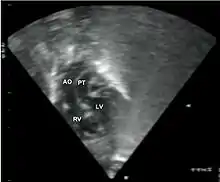

قد يكشف مقدم الرعاية الصحية عن لغط قلبي أثناء الاستماع إلى الصدر بالسماعة الطبية، ويكون لون جلد الطفل وفمه أزرقًا. وغالباً ما تشمل الاختبارات ما يلي:

- الأشعة السينية على الصدر، الأشعة السينية على الصدر، تحول الأوعية الكبرى يظهر عادة صورة ظلية للقلب المنصف على أنها "بيضة على سلسلة"، حيث القلب المتوسع يمثل بيضة على الجانب والغدة الصعترية الضامرة من المنصف العلوي تمثل السلسلة.

- مخطط صدى القلب (إذا تم ذلك قبل الولادة، يُسمى مخطط صدى القلب الجنيني)